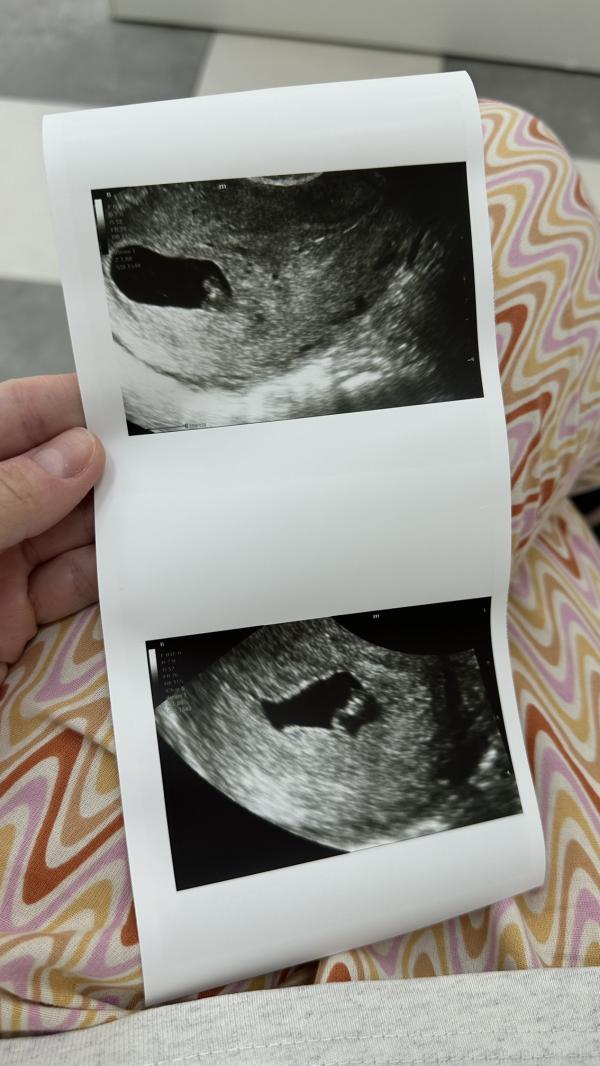

Сходила я на узи, тревожная мать🙈 Все хорошо, сердечко стучит на узи она разглядывала, говорит что как будто есть перегородка, но второго эмбриона нет, сказала что либо в начале должен был быть, или появится ещё🙈 Какова вероятность что сейчас нету, а потом появится второй? Уже 7,4 недели

(На втором фото видно перегородку)